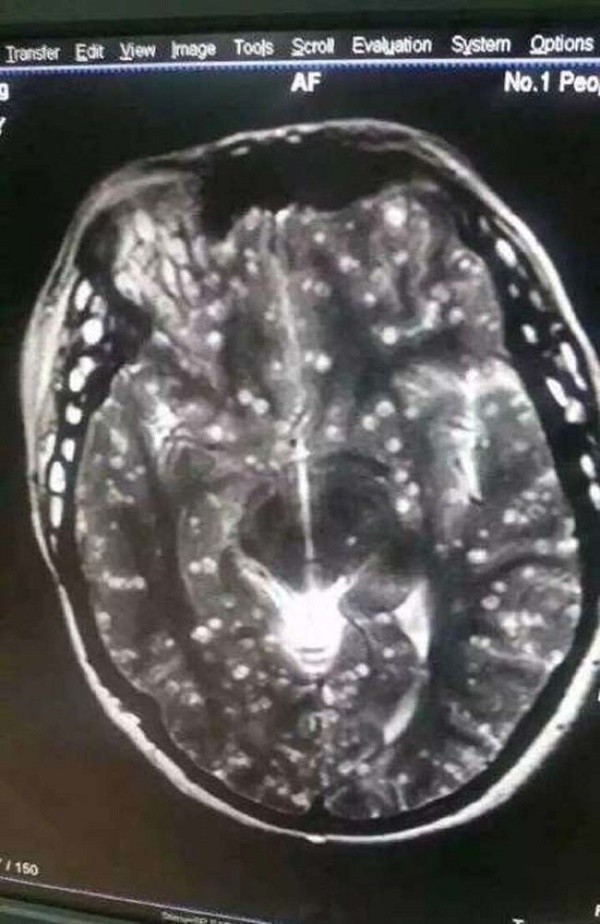

Bộ não bị trứng của giun sán chiếm lĩnh.